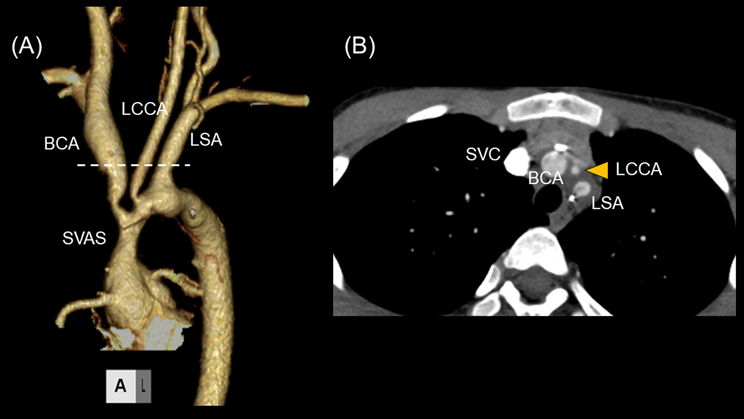

Transthoracic echocardiography revealed multiple vegetations in the aortic arch (Fig. 1). Thoracic contrast-enhanced CT indicated not only SVAS but also stenosis at the origin of either the brachiocephalic artery or the left common carotid artery (Fig. 2). At the time of admission, the patient also experienced left-sided abdominal pain and nausea. Abdominal contrast-enhanced CT revealed renal and splenic infarctions without any arterial aneurysm (Fig. 3). Magnetic resonance imaging (MRI) revealed a very small brain hemorrhage scar. Blood culture detected Abiotrophia defectiva, an endemic oral bacterium that shows penicillin sensitivity. We made a diagnosis of IE according to the modified Duke criteria.4) Urgent surgery for removing vegetations was performed to avoid cerebral embolisms, followed by antibiotic therapy using both penicillin 300,000 U/kg/day and Gentamycin 3 mg/kg/day.

Fig. 1 Transthoracic echocardiography shows multiple mobile vegetations in the aortic arch. (A) The greatest vegetation is 7×4 mm in size. (B) Four vegetations are at the root of the left subclavian artery

AA, aortic arch; LCCA, left common carotid artery; LSA, left subclavian artery.